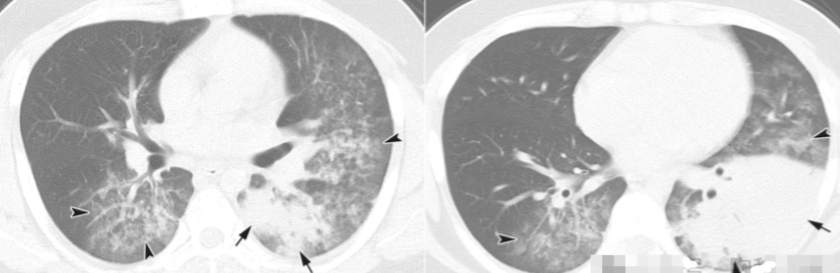

由鼻病毒引起的肺炎显示多个边界不清的GGO斑片状区域(箭),两肺小叶间隔增厚(箭头)。

图示为典型的鼻病毒性肺炎的CT表现。